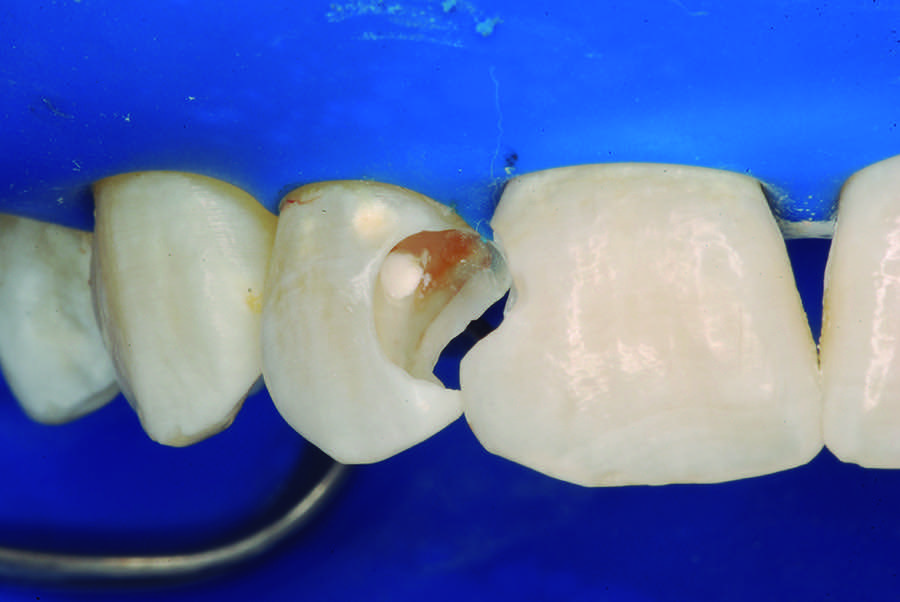

The partial pulpotomy was performed for tooth No. 7 due to the pulp exposure during the caries removal procedures (Figure 5). The superficial contaminated pulp tissue was removed with a No. 1012 spherical diamond bur at high speed with water cooling to allow a better reparative response. This procedure was limited to removal of the infected dentin and damaged pulp tissue, removing the injured odontoblast cell layer. During this step, the remaining pulp tissue was analyzed and found to have good consistency and abundant red bleeding (Figure 6). After the pulpotomy, a solution of calcium hydroxide was used for irrigation along with a sterile cotton pellet to achieve hemostasis and disinfection. After hemostasis, the tooth was treated with direct pulp capping: the exposed area was covered with calcium hydroxide powder (Figure 7) and calcium hydroxide cement (Figure 8). The cavity was provisionally restored with the use of a restorative GIC (Figure 9).

Fig 5. Partial pulpotomy with No. 1012 diamond bur under water cooling.

Figure 5

Fig 6. Aspect of the pulp after partial pulpotomy, showing the abundant red bleeding.

Figure 6